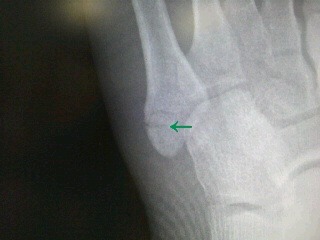

亀裂骨折はどれぐらいの期間で完治しますか?

ギプスを巻いて1ヵ月、その後、リハビリをしてトータル2,3か月程度かかります。

通常の治療方法:骨折の治療で一般的なのは、ギプスです。